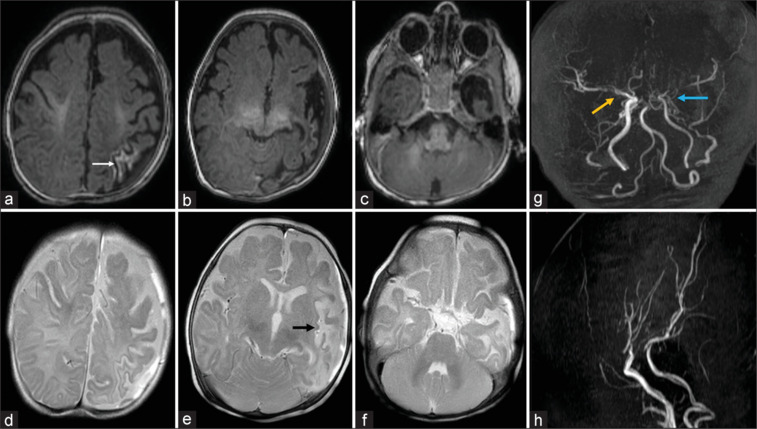

Moyamoya disease in early infancy: Report of youngest Indian infant.

婴儿期早期烟雾病:印度最年轻婴儿报告。